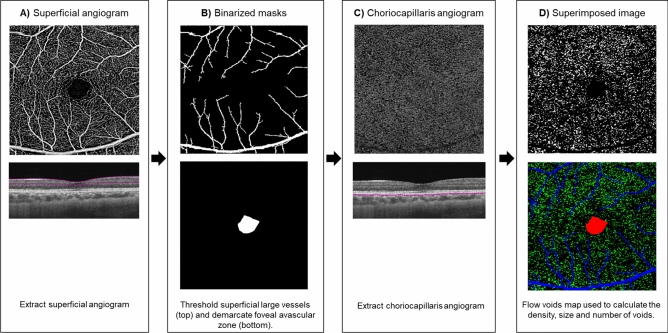

Evaluation of the retinal vasculature and the choriocapillaris flow voids

The choriocapillaris flow voids were generated based on a previously published imaging-processing algorithm using MATLAB (Fig. 4)11. First, superficial vascular plexus, deep vascular plexus and choriocapillaris angiography images were extracted from the OCTA device. The superficial vascular plexus image was taken from the segmentation from the inner limiting membrane (ILM) to the inner plexiform layer (IPL), the deep vascular plexus image was taken from the IPL to the outer plexiform layer (OPL) while the choriocapillaris image was taken from 31 µm below the retinal pigment epithelium (RPE) to 40 µm below the RPE. We further assessed the B-scans for any evidence of segmentation errors. Segmentation errors were defined as the incorrect identification of the retinal layers by the software. Second, projection artifacts from the overlying retinal circulation were removed from the deep vascular plexus and choriocapillaris images using the removal software that was integrated with the PLEX Elite 9,000 instrument. Projection artefacts of the overlying superficial vascular angiogram may inadvertently be included as a “flow void” if these were not removed from the calculation of flow voids. We excluded the potential noise from the flow voids calculation by excluding the large vessels from the superficial plexus and FAZ, thus providing robust data for the analysis of choriocapillaris, as compared to the other studies which did not exclude the influence of projection artefact14,15. Two masks from the superficial vascular plexus angiogram were created (Fig. 4B)—one was of the larger vessels11,38 and the other foveal avascular zone (FAZ). An intensity-based threshold was applied to generate a binarized mask of the large vessels. Third, we manually demarcated the FAZ. Afterwards, we overlaid the two masks over the choriocapillaris angiogram to remove the influence of the larger vessels and FAZ from the calculation of flow voids (Fig. 4D). We excluded the choriocapillaris flow voids measurements within the FAZ region because of two reasons. First, in healthy eyes, the flow voids in the FAZ region were less detectable than those outside the FAZ region39. Second, in myopic eyes, the flow voids tended to be more reduced within the foveal area, than the para- or peri-foveal regions34. Considering that all our participants are myopic, we wanted to perform the analysis that would be less affected by myopia and more generalizable to general population. Fourth, the flow voids were calculated using the 1 standard deviation (SD) thresholding strategy12. The flow voids were calculated as the non-perfused area divided by the area of the image excluding the large vessel and FAZ areas. The total number of flow voids were also counted, and average sizes computed as the total sizes of flow voids divide by the total number. A single flow void is defined as an unconnected object in the binarized choriocapillaris image. All flow voids analyses were evaluated for 14 subjects, where one subject has been excluded because of poor image quality.

Figure 4.

Algorithm for artefact removal and calculation of features of choriocapillaris flow voids. The angiograms and B-scans images were generated from the built-in review software (PLEX Elite Review Software, Carl Zeiss Meditec, Inc., Dublin, USA; Version 1.7.1.31492; https://www.zeiss.fr/content/dam/Meditec/international/ifu/documents/plex-elite/current/2660021169042_rev._a_artwork.pdf).